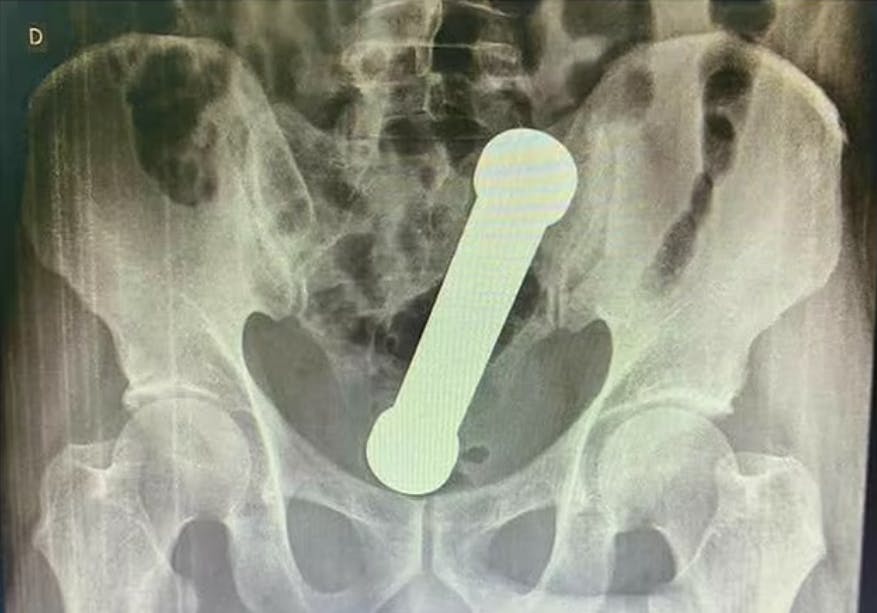

Håndvægten med en længde på 20 centimeter og en vægt på to kilo blev ført op i endetarmen.

Håndvægten sad fast oppe i mandens tarm. Og det gjorde den i to dage!!

Lægen måtte altså indføre sin underarm i mandens endetarm for at fjerne håndvægten.

Og så skete der ting og sager. Endelig lykkedes det at fjerne objektet.

Det var en noget vanskelig fødsel af håndvægten, skrev de, og manden blev udskrevet efter tre dage på hospitalet.